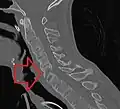

X-ray showing bamboo spine in a person with ankylosing spondylitis

CT scan showing bamboo spine in ankylosing spondylitis

The earliest changes demonstrable by plain X-ray shows erosions and sclerosis in sacroiliac joints. Progression of the erosions leads to widening of the joint space and bony sclerosis. X-ray spine can reveal squaring of vertebrae with bony spur formation called syndesmophyte. This causes the bamboo spine appearance. A drawback of X-ray diagnosis is the signs and symptoms of AS have usually been established as long as 7–10 years prior to X-ray-evident changes occurring on a plain film X-ray, which means a delay of as long as 10 years before adequate therapies can be introduced.[24]

"Bamboo spine" develops when the outer fibers of the fibrous ring (anulus fibrosus disci intervertebralis) of the intervertebral discs ossify, which results in the formation of marginal syndesmophytes between adjoining vertebrae.